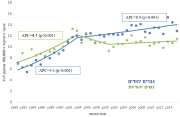

| 11:51, 13 באוגוסט 2023 | סוכרת במבוגרים 6.png (קובץ) |  |

253 קילו־בייטים | Motyk | 1 | |

| 11:47, 13 באוגוסט 2023 | סוכרת במבוגרים 5.png (קובץ) |  |

198 קילו־בייטים | Motyk | 1 | |

| 11:22, 13 באוגוסט 2023 | סוכרת מבוגרים 3.png (קובץ) |  |

132 קילו־בייטים | Motyk | 1 | |

| 11:17, 13 באוגוסט 2023 | סוכרת מבוגרים 2.png (קובץ) |  |

498 קילו־בייטים | Motyk | 1 | |

| 10:25, 13 באוגוסט 2023 | סוכרת מבוגרים 1.png (קובץ) |  |

684 קילו־בייטים | Motyk | 1 | |